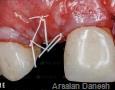

Surgery